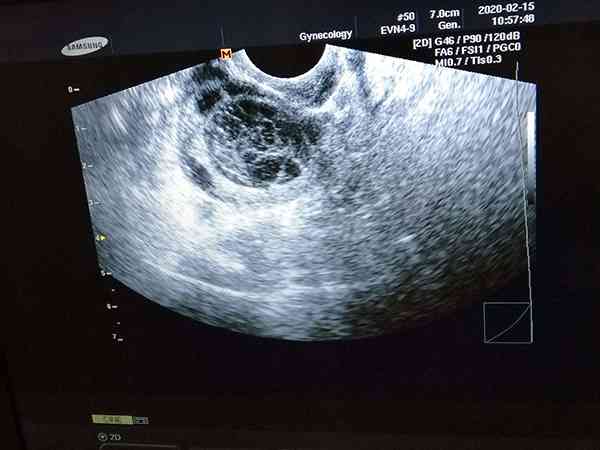

優勢卵泡是直徑在10-18mm之間的卵泡,需要繼續發育才能稱為成熟卵泡,成熟卵泡的標準是直徑在18-25mm之間,卵泡成熟之後和精子相遇成功受孕的機率比較大,想要自然懷上三胞胎的概率是很小的,而且也不是所有人都適合。

孕育多胎是比較困難的,自然懷上雙胞胎的機率都只有3%,三胞胎更是少的可憐,雖然說這種情況可能真實存在,但幾乎可以忽略不計,如果說女性想知道自己體內有3個優勢卵泡,到底能不能成功懷上三胞胎,主要要分以下幾種情況: